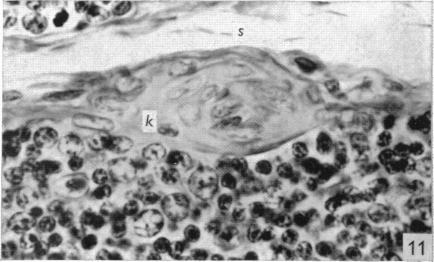

The effect of castration, oestrogens, testosterone and the oestrous cycle on the cortical epithelium of the thymus in male and female rats.

J Anat. 1968 Jun;103(Pt 1):113-33.